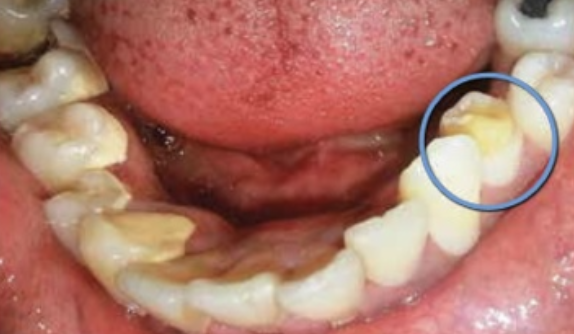

Wat is een pulpa poliep?

Een pulpa poliep of chronische hyper plastische pulpitis, is het gezwollen roze ontstoken weefsel dat te zien groeien is in de mondholte van een open ruimte aan de buitenzijde van de tand. Het is een aandoening die niet vaak voorkomt en dan uitsluitend bij kinderen en jonge volwassenen met sterk carieuze elementen waarbij een opening aanwezig is van de pulpakamer. Het granulatieweefsel in de pulpaholte woekert door de opening naar buiten waarna het geëpitheliailiseerd wordt. De patiënten hebben geen pijnklachten en manipulatie van de pulpa poliep is niet pijnlijk omdat het granulatieweefsel niet geïnnerveerd is. Manipulatie kan wel aanleiding geven tot een bloeding, omdat het granulatieweefsel doorgaans goed gevasculariseerd is. Een goede vascularisatie van de pulpa en een wijd foramen apicale gecombineerd met een grote weefselweerstand zijn noodzakelijk voor het ontstaan van een pulpapoliep.